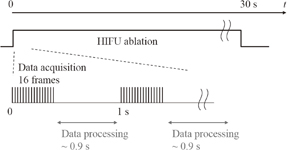

Standard image High-resolution imageSixteen frames (corresponding to one period of LMI oscillation) of RF data obtained by an ultrasound scanner were acquired within 0.05 s in every 1 s. The computation time for data processing including cross-correlation was within 0.9 s. This sequence is shown in Fig. 6. HIFU ablation time was controlled using a gate circuit based on the results of LMI. The target was porcine liver tissue embedded in polyacrylamide gel. The experiments were conducted at room temperature. In this experiment, the AM frequency was 168 Hz. The HIFU frequency and intensity were 2.2 MHz and 1.2 kW/cm2, respectively. The beam propagation distances L shown in Fig. 7 are 10, 20, and 30 mm. The experiments were conducted as follows:

Fig. 6. Timing diagram for real-time measurement.

Download figure: